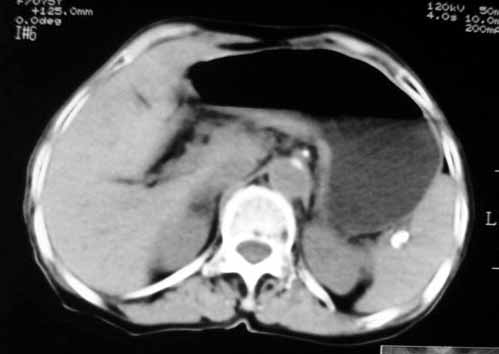

腹膜后软组织肿块,密度不均匀,病灶分叶,降主动脉受浸犯

考虑来源于腹膜后间叶组织的肿瘤

脂肪肉瘤,平滑肌肉瘤的可能性大

1.中腹部腹主动脉旁可见巨大包块影,其形态似为2个(或分叶),与腹主动脉分界不清,边界较清,其内密度不均匀(稍高、不匀称低密度),腹膜后未见确切肿大淋巴结...性质?考虑腹主动脉瘤可能性大,不排除平滑肌瘤及畸胎瘤可能,建议增强ct;

2.脾门处高密度影块影,原因?

3.右肾前外极囊性低密度影,边界清楚,考虑肾囊肿可能。

考虑:1、左侧腹膜后占位性病变(以间叶源性肿瘤可能性大);

2、右肾上极小囊肿;

3、脾门区淋巴结钙化。

脂肪肉瘤,平滑肌肉瘤的可能性大。支持!(本例关键是定位,仔细分析,可以观察到主动脉被包埋于肿瘤内,因此可定位于—来源于腹膜后的实性肿瘤。)

腹膜后肿块侵犯腹主动脉及肠系膜上动脉,肿块密度不均,1来源间叶组织肿瘤,2肠系膜恶性肿瘤可能大,